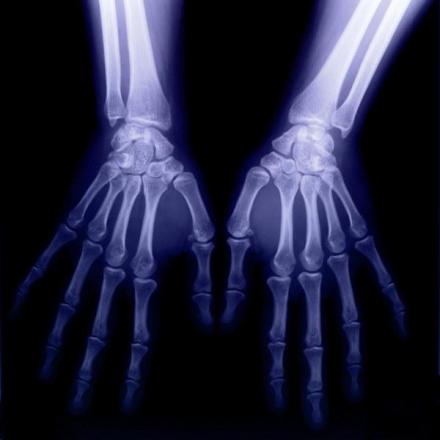

双手X光图片

1、感光作用。X射线同可见光一样能使胶片感光。胶片感光的强弱与X射线量成正比,当X射线通过人体时,因人体各组织的密度不同,对X射线量的吸收不同,胶片上所获得的感光度不同,从而获得X射线的影像 。

X射线应用于医学诊断,主要依据X射线的穿透作用、差别吸收、感光作用和荧光作用。由于X射线穿过人体时,受到不同程度的吸收,如骨骼吸收的X射线量比肌肉吸收的量要多,那么通过人体后的X射线量就不一样,这样便携带了人体各部密度分布的信息,在荧光屏上或摄影胶片上引起的荧光作用或感光作用的强弱就有较大差别,因而在荧光屏上或摄影胶片上(经过显影、定影)将显示出不同密度的阴影。根据阴影浓淡的对比,结合临床表现、化验结果和病理诊断,即可判断人体某一部分是否正常 。